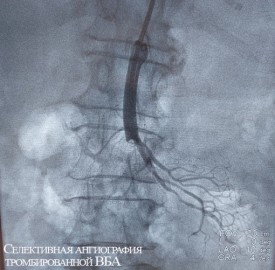

В НМИЦ им. В. А. Алмазова врачи смогли предположить такой диагноз, который подтвердился в обоих случаях после срочного выполнения анализов и компьютерной томографии. Получив результаты обследований, эндоваскулярные хирурги и врачи отделения хирургических методов лечения онкологических больных приняли совместное решение о необходимости экстренной операции.

Обеим женщинам было выполнено эндоваскулярное вмешательство — без разрезов, через прокол в бедренную артерию в паху был введен зонд, с помощью которого врачи удалили тромбы из просветов сосудов. Обе пациентки были в сознании во время операции, и прямо на операционном столе у них прошел болевой синдром.

«В ситуации, когда мы имеем дело с острым нарушением кровообращения в кишечнике, пациенты могут сначала жаловаться на боль в животе, рвоту. Но немного позже боль начинает отступать. Это значит, что нервные волокна, которые имеет кишечник, уже поражены некрозом. Поэтому такой сигнал может быть очень тревожным», — комментирует заведующий НИЛ интервенционной хирургии, врач по рентгенэндоваскулярным диагностике и лечению отделения рентгенохирургических методов диагностики и лечения, врач — сердечно-сосудистый хирург к.м.н. Артем Викторович Горбатых.